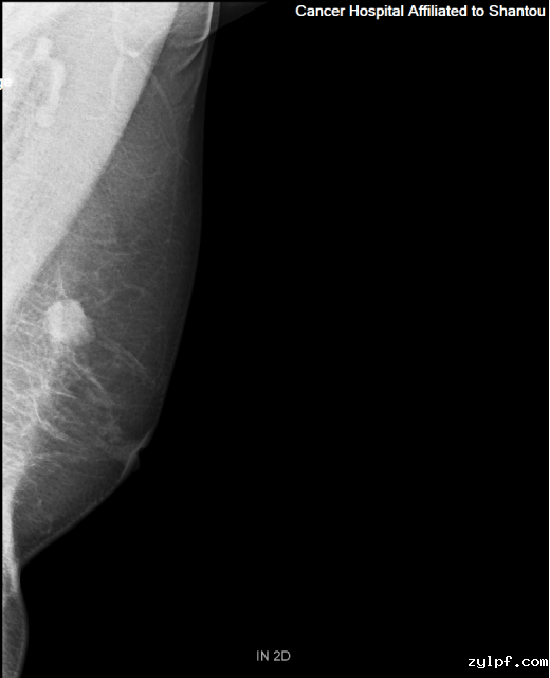

乳腺钼靶.png

乳腺钼靶